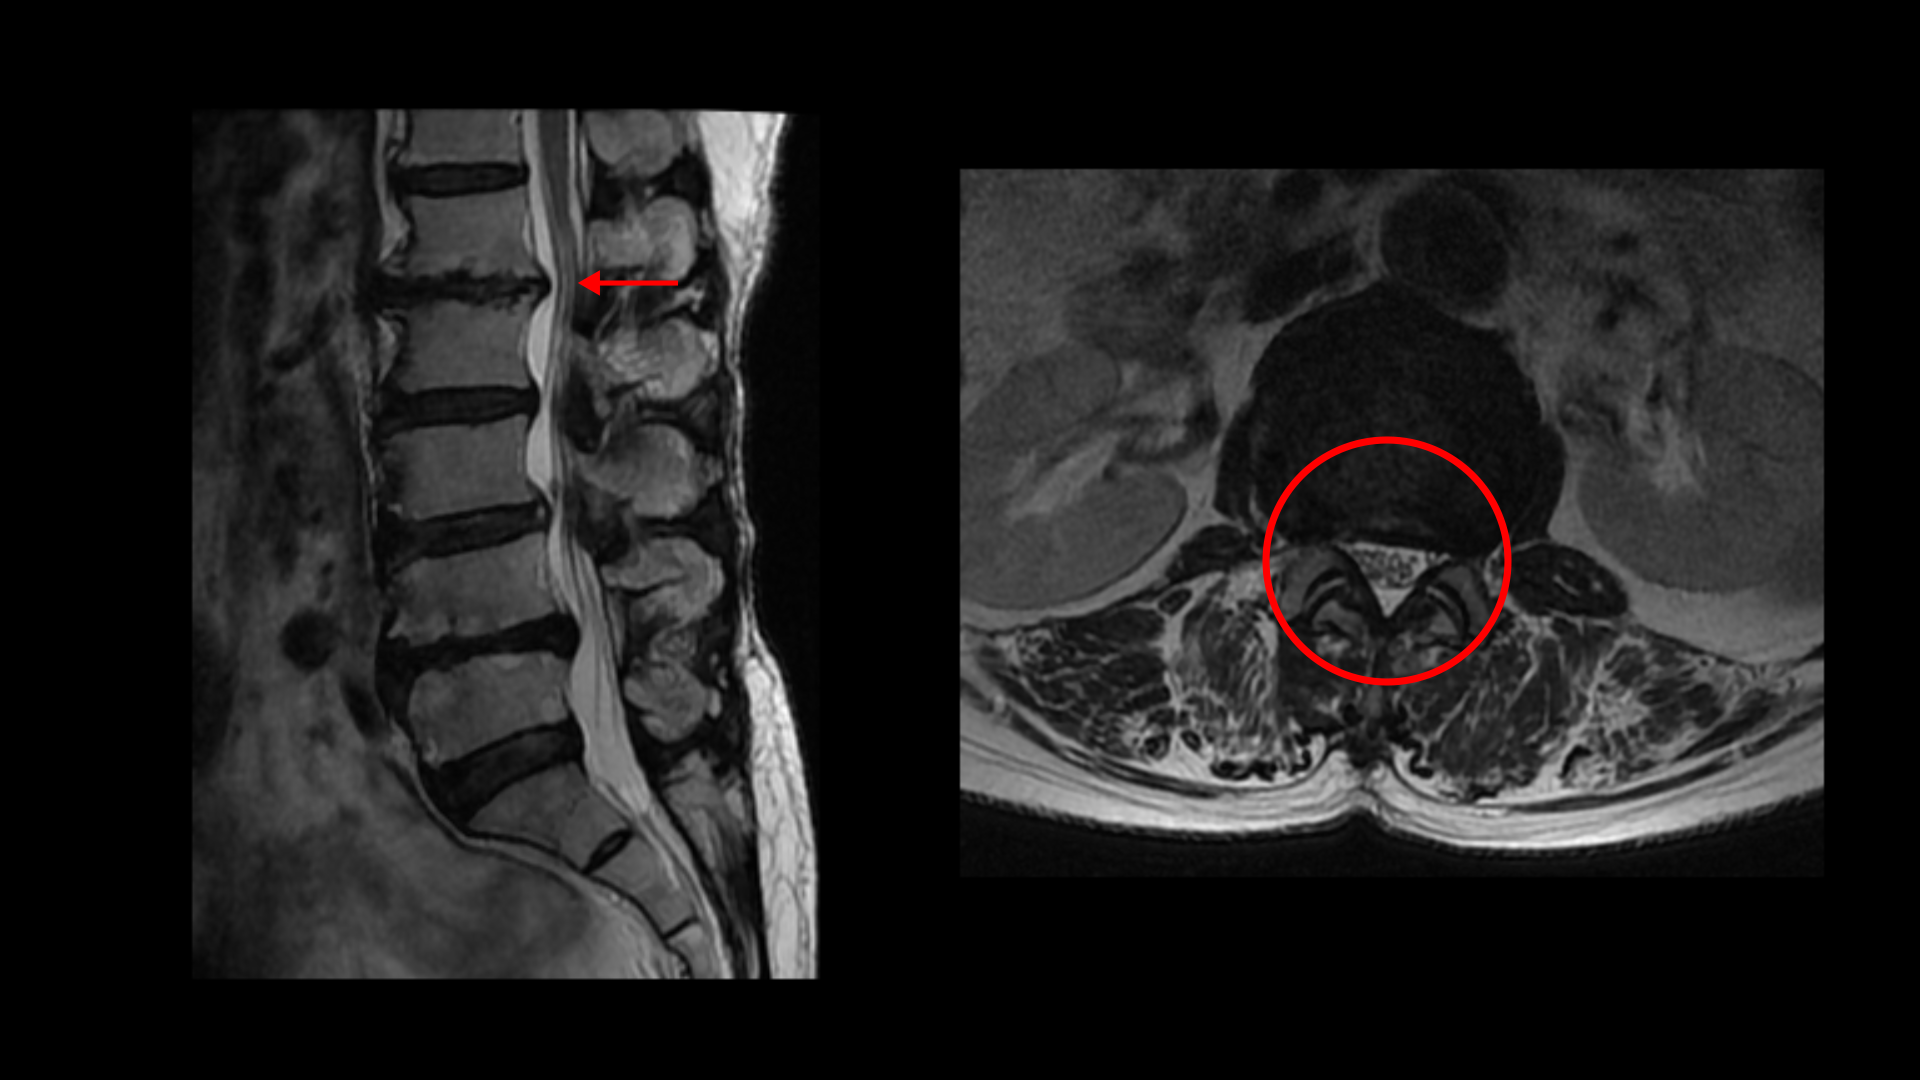

이분 MRI를 보면 허리 다섯 마디에 전부 퇴행성 디스크가 있습니다.

1-2번에는 오른쪽으로 디스크도 밀려 나와 있고 중심성 협착도 있습니다.

2-3번에는 왼쪽으로 신경구멍 쪽으로 디스크가 밀려 나와있습니다.